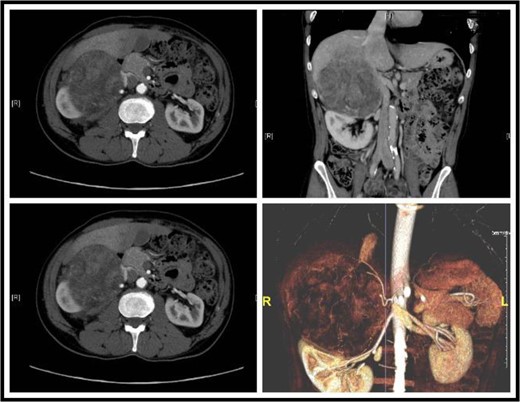

Sections of the CT showing a large retroperitoneal mass, focal absence of fat gland and an invasion into the liver.